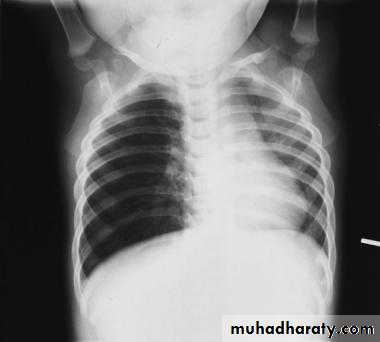

CXR: shows signs of hyperexpansion of the lungs, including increased lung radiolucency and flattened or depressed diaphragms. Areas of increased density may represent either viral pneumonia or localized atelectasis.